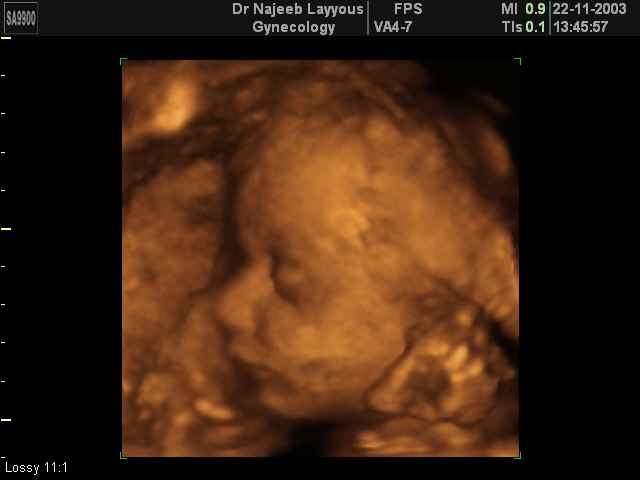

The baby's breathing movements begin and fat deposits under the skin, which then makes the baby seem wrinkled. Mother expierences fetal movements and total weight gain is about 10-12 pounds.

-